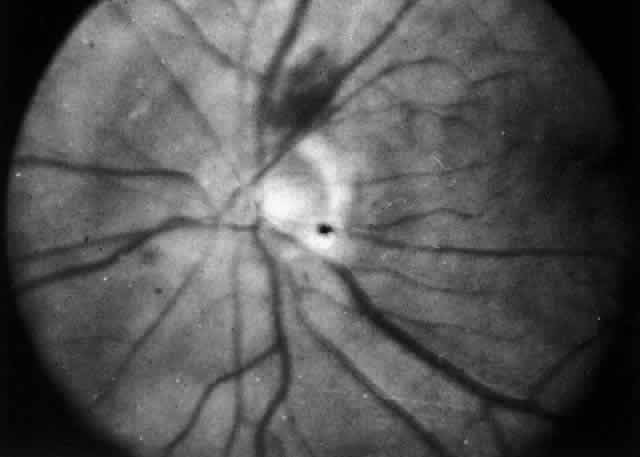

Fig. 52. Fundus appearance after resolution of exudative detachment in patient with

severe posterior scleritis. Macula was affected and vision much impaired. (Watson PG: Management of scleritis. In: Recent Advances in Ophthalmology, Vol 5. London, Churchill-Livingstone, 1975) Fig. 52. Fundus appearance after resolution of exudative detachment in patient with

severe posterior scleritis. Macula was affected and vision much impaired. (Watson PG: Management of scleritis. In: Recent Advances in Ophthalmology, Vol 5. London, Churchill-Livingstone, 1975)

|

at some stage in the disease. As the scleral disease is brought under control, the uveitis resolves, leaving

anterior and posterior synechiae unless care is taken to prevent

them. The inflammation of the pars plana sometimes leads to massive

pigment migration at the retinal periphery, leaving a reaction rather

like a diathermy or cryotherapy reaction in retinal detachment surgery (see Fig. 52). Glaucoma The intraocular pressure may become raised at any stage of the disease

Retinal Detachment Exudative retinal detachment occurs in patients who have posterior scleritis, and

it may, indeed, be the only sign in a very painful eye. The

detachment is poorly mobile. A pale gray granuloma can be seen extending

from the choroid beneath the retina and is accompanied by a poorly

mobile serous detachment that may become total. The scleral granuloma

sometimes leaves a permanent, inward indentation of the retina and a

subretinal mass, although this does not always occur. An increasing hypermetropia

has also been noted; it is of rapid onset (over a period of 1 week) and

is caused by the diffuse scleral edema in the early stages

of the disease before the detachment of the retina occurs. The exudative detachment usually resolves completely with treatment of

the scleritis. However, if the inflammatory changes have affected the

macular area, vision will be severely and permanently affected. After

resolution, the retina shows a diffuse, heavy pigmentation of the affected

area with a “high-water mark” at the edge (see Fig. 52). Patchy changes outside this area do not seem to occur. Surgery is not